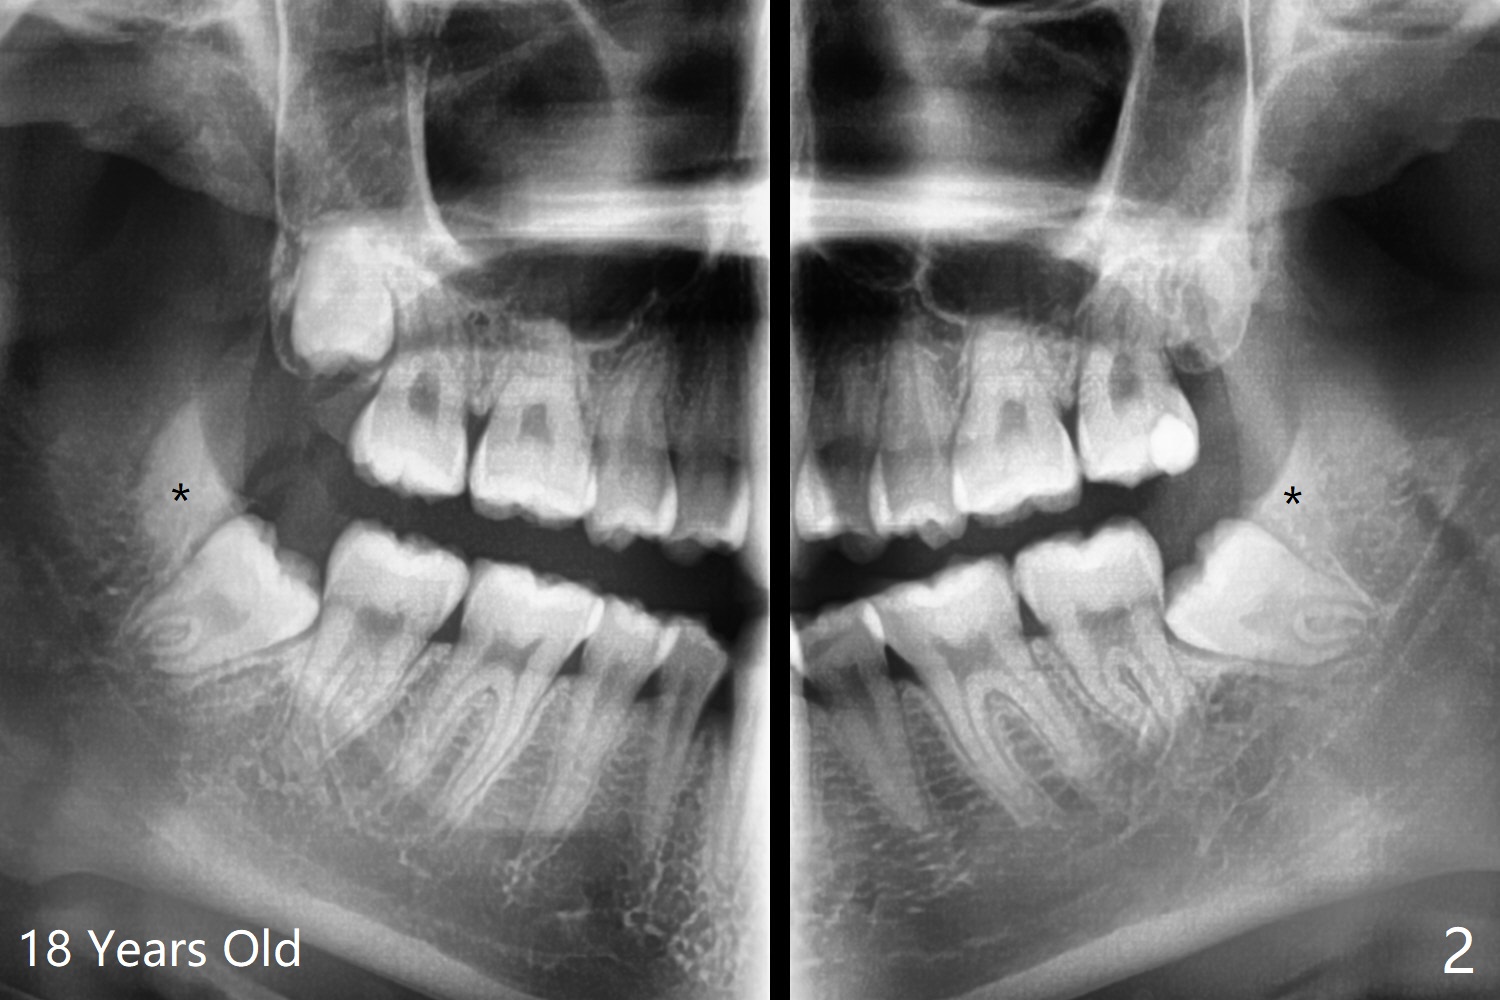

15岁女孩外斜嵴好像小三角形,骨质密度低(图一),18岁时三角形变大,密度增高(图二)。术前拍摄小范围CT,术中切开后,拍摄照片显示外斜嵴,随着颊侧去骨,嵴被破坏(拍照)。

由于临床忙,没有术前拍摄CT,术中发现外斜嵴两侧都不明显(女孩原因?),拔除两侧都需要颊侧去骨。由于左侧智齿颊侧阻生(图三:*),拔除后两侧都放置骨水泥(Bond Apatite,图四:A)促进骨修复,口腔卫生欠缺,可能容易形成牙周炎。